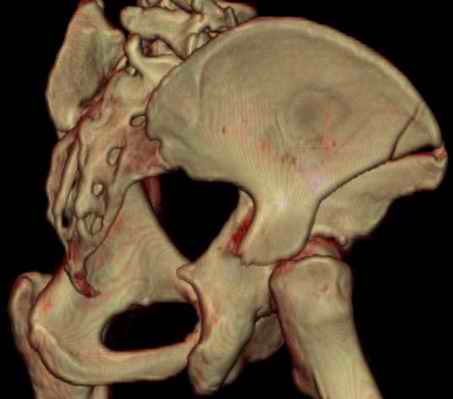

Посылаю схемы и 3D реконструкцию подобного повреждения. Называется он полным высоким двухколонным переломом вертлужной впадины, а "переломы крыла и тела подвздошной кости" входят в это понятие.

Вариантов остеосинтеза много (можно и не оперировть, т.к. конгруентность при таких переломах как правило сохраняется)

прикладываю схему доступа и случай.